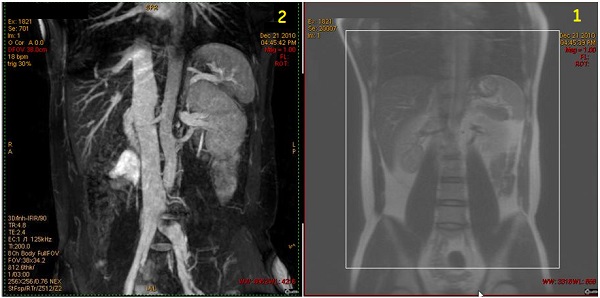

Figure 4. Coronal localizer with IR band and resultant coronal renal image

Table 2. Image legend

NumberDescription

1Coronal localizer with large axial IR band (red box) applied inferior to saturate venous flow.

2Resultant Inhance Inflow IR coronal image of renal artery .